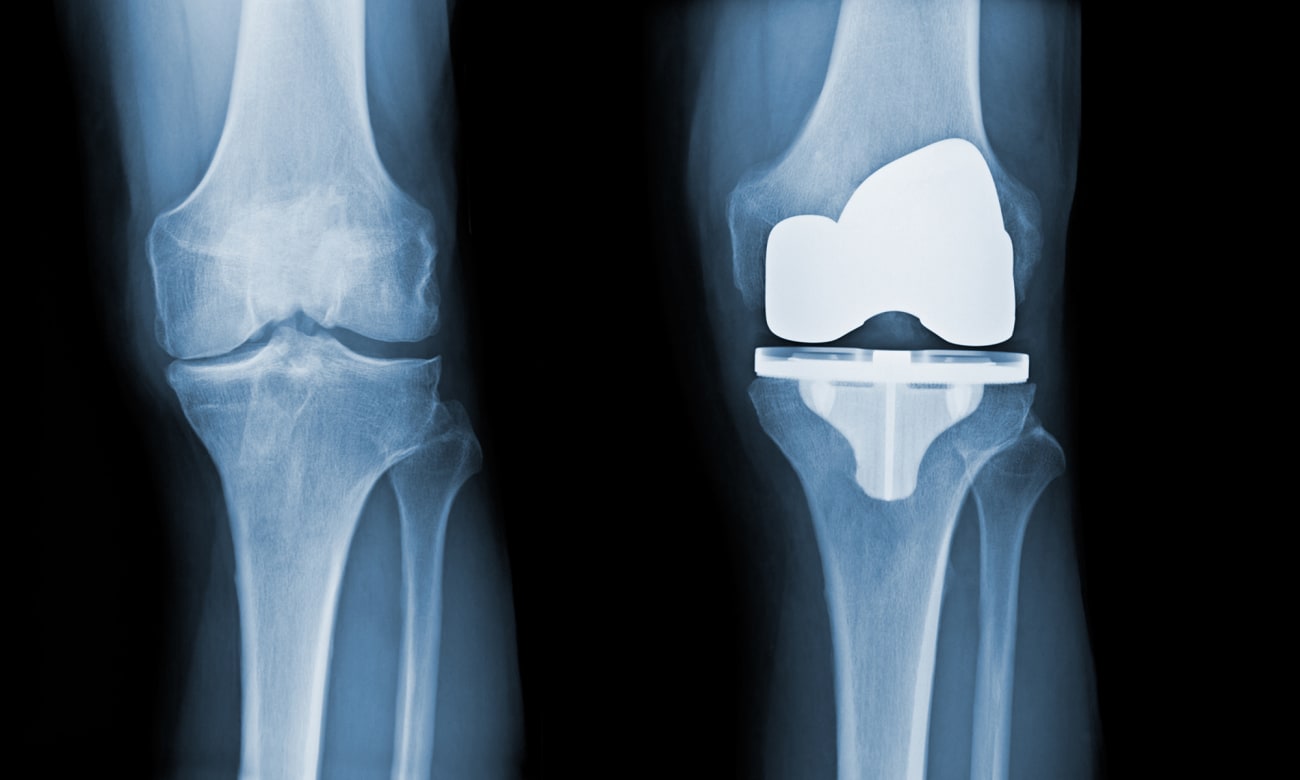

Despite the high success rates of the most common total joint replacements — those on the knee and hip — 2% to 5% of patients have complications from these procedures, says Johns Hopkins orthopaedic surgeon Savyasachi Thakkar.

Some of these complications, such as heart attacks, strokes, and respiratory issues that necessitate intubation, result from anesthesia given during these procedures; others, including infections, fractures, implant failure or loosening, and unexplained pain that develops during healing, result from the procedure itself.

In 2022, Thakkar and his colleagues published a study in The Journal of Arthroplasty examining complication rates in patients who had bilateral total knee replacements. Although operating on both knees during the same procedure reduces the risks associated with anesthesia, it may present mobility challenges for some patients. So, most patients who need bilateral knee replacements choose to have these bilateral arthroplasties as two separate procedures. However, the ideal timing between the two surgeries to reduce complications has been unknown.

To answer this question, Thakkar and his colleagues examined records acquired from a national insurance database from more than 25,000 patients who had bilateral total knee replacements in 2015 to 2018. Their findings show that having the second procedure at least six weeks after the first significantly reduced complication rates compared to having the second procedure earlier.

In a third 2022 study, published in The Knee, Thakkar’s team compared complication rates between patients who had total knee replacements and those who had partial replacements. The findings show that patients who had unicompartmental and bicompartmental arthroplasty were more likely to need revision procedures within the next two years than those who had total knee replacements. However, patients with partial knee replacements were less likely to experience postoperative complications in the 90 days after surgery than those who had total knee arthroplasty.